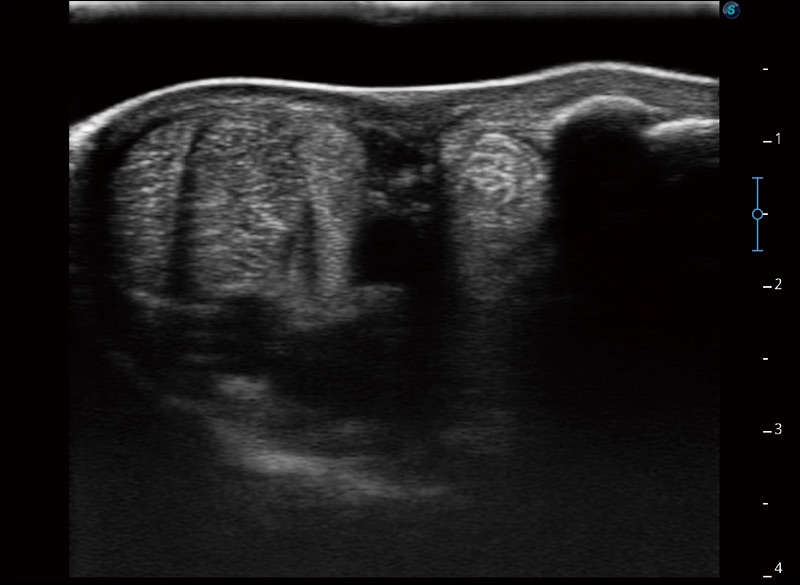

任意波束合成技術(shù)

在不犧牲時(shí)間分辨率的情況下提供出色的圖像

空間復(fù)合成像

優(yōu)化不同角度的圖像